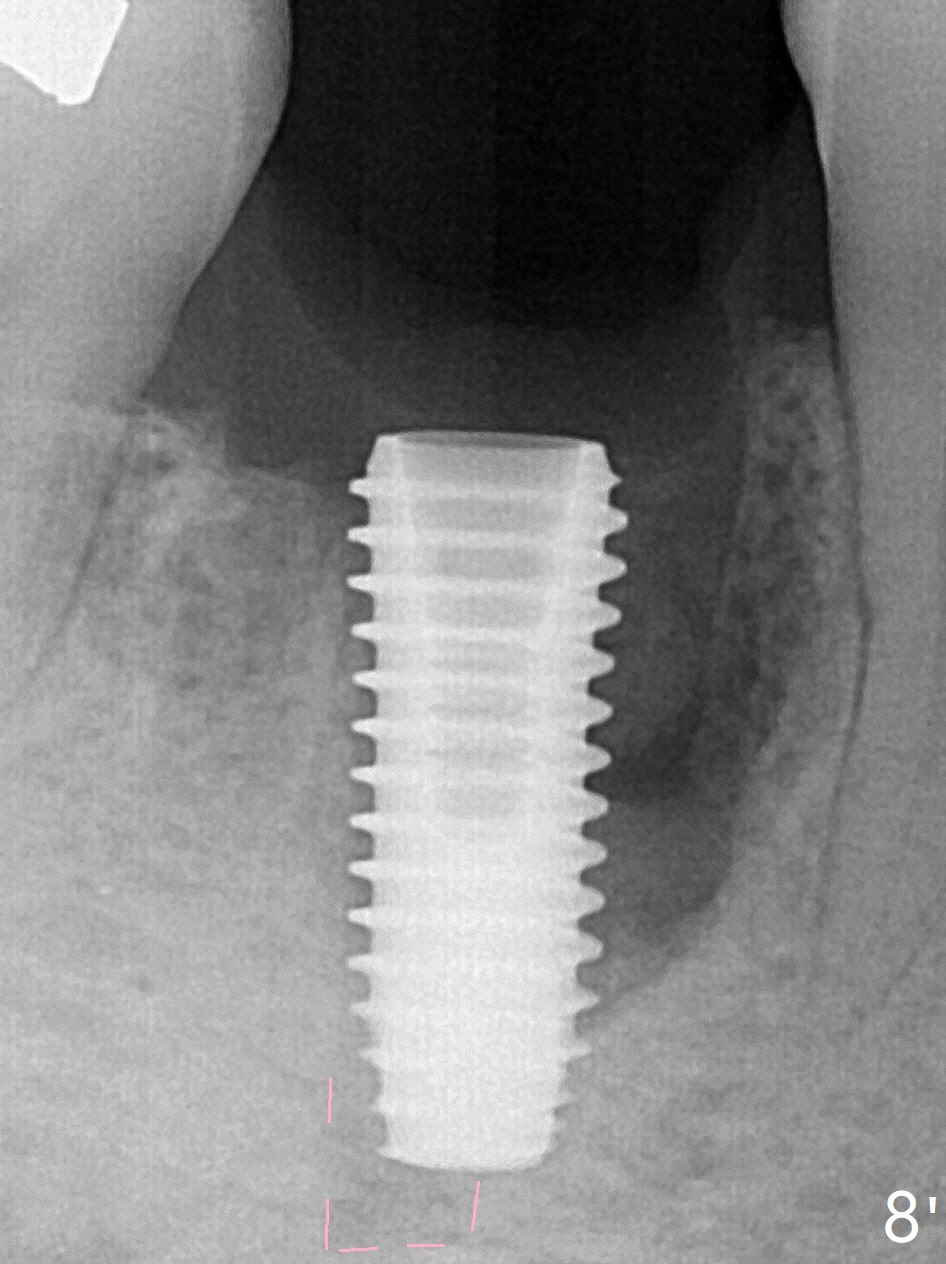

Preop oral Amoxicillin seems to be associated with reduction in the buccal and lingual (Fig.3 arrow) fistulae at #30, but there is mesiobuccal swelling (Fig.1 *) with 7 mm pocket (Fig.2). Osteotomy is initiated in the middle of the septum (Fig.3-5 S). As the osteotomy increases, it shifts mesially (Fig.6 arrow). Guided surgery is able to reduce shifting. A 5x13 mm implant is not seated completely (Fig.7) apparently due to osteotomy shifting. After removal of the bone from the osteotomy distally, the implant remains unseated with lower torque value (Fig.8). Following reuse of the 4.3 mm drill deeper by 1-2 mm, the implant is seated to a satisfactory depth (Fig.9 with increase in torque to 50 Ncm) with placement of Vera Graft (*) and a 7.5x4(3) mm abutment. After a second round of allograft placement (Fig.10 *), the implant is found to be 4 mm from the IAC. At the later stage of osteotomy, the coronal end of the septum is destroyed with loss of osteotomy depth landmark. It is apparent that the soft tissue landmark may be more reliable. The implant threads appear to be covered by the bone graft 3.5 months postop (Fig.11). The abutment is changed to 6.5x5(3) mm one before impression with minor margin prep. The bone density seems to increase 5 months postop, i.e., immediately post cementation (Fig.12) and 10 months postop (5 months post cementation (after retightening abutment), Fig.13 (*)). Periimplantitis develops mesiobuccally, consistent with bone loss 1 year 7 months post cementation (Fig.14 *); the implant seems to have been buccally placed. Bone graft is necessary with PRF or GEM21S if the vein is small and 6-month membrane with a hole around a 7.5x4(4) cemented abutment for easy wound closure. Take 5x5 CM CBCT to determine which wall has defect, buccal or lingual. Check mesial contact. If so, remove the crown, reseat the abutment (possible incomplete seating) and re-impress after bone graft.